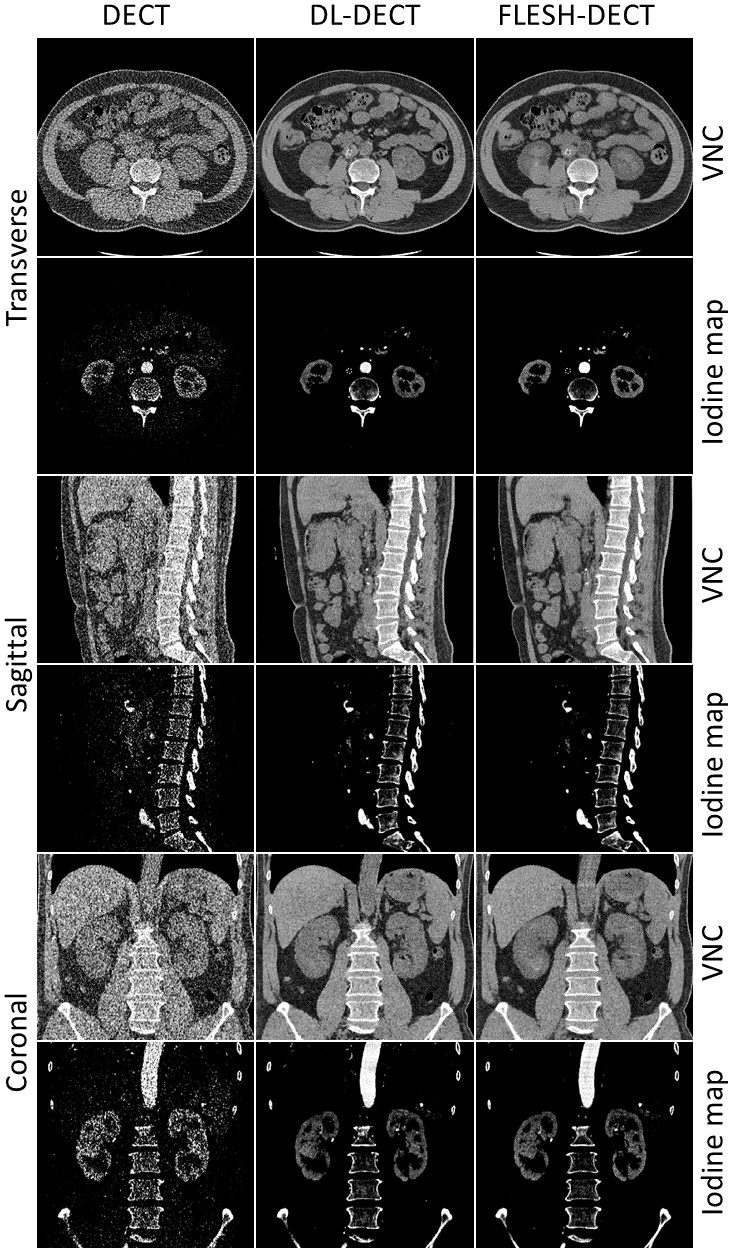

Figure 8: VNC images and Iodine maps reconstructed using original DECT, DL-DECT, and FLESH-DECT images. The first, third and fifth row are the VNC images on axial, sagittal and coronal view, respectively, while the second, fourth and sixth row are the corresponding Iodine maps.

In our previous work [47], we propose the DL-DECT method to estimate Idifsubscript𝐼𝑑𝑖𝑓I_{dif} directly from Ilowsubscript𝐼𝑙𝑜𝑤I_{low}. In this work, with the introduction of the additional high-energy single-view projection, we can further enhance the accuracy of the predicted high-energy image and eventually the accuracy of the material- and energy-specific images. To show the benefit of the additional high-energy projection, we quantitatively compared the proposed FLESH-DECT method with the DL-DECT method. Virtual noncontrast (VNC) images and iodine maps are derived to demonstrate the clinical utility of the proposed method. Fig. 8 depicts the VNC images and iodine maps reconstructed using different methods on the transverse, sagittal and coronal planes. Both the DL-DECT and FLESH-DECT algorithms provide high-quality VNC and iodine images that are consistent with the images generated by original DECT images. Quantitative metrics on VNC and iodine images are shown in Table 2. The results demonstrate FLESH-DECT can provide high-quality material-specific images and it outperforms the DL-DECT method.

From the VNC images and Iodine maps, we find that the DL-derived VNC images and iodine maps show a remarkably reduced noise level compared with those generated from original DECT images. Here we also compare the noise level by calculating the standard deviation in ROIs. More than 500 ROIs were selected randomly in homogeneous areas. The mean standard deviations in ROIs on each testing patient are provided and compared in Table 3. The mean standard deviations of the images derived using FLESH-DECT are close to that of the DL-DECT method which is much lower than those from the original DECT images. This result shows that the FLESH-DECT method maintains the denoising feature.